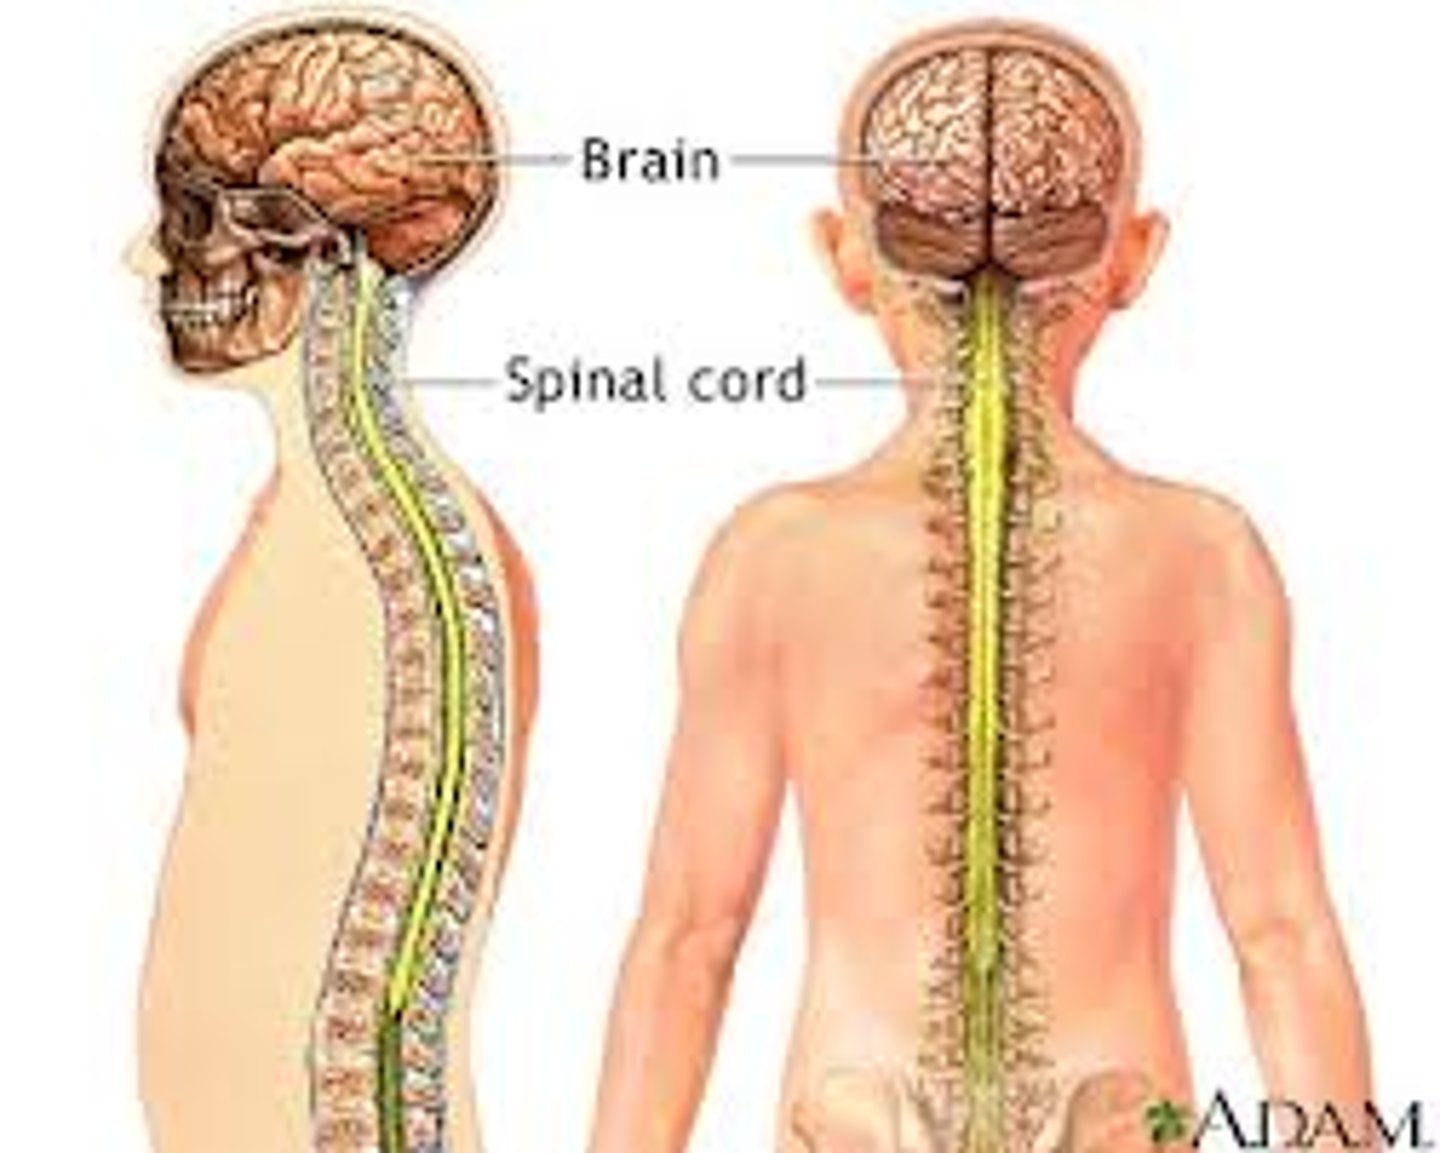

What is the nervous system?

Consists of the brain, spinal cord & nerves & it serves as the body's CONTROL SYSTEM. Once a threat is detected the nervous system activates appropriate muscles or glands to respond. Sensor for HOMEOSTASIS